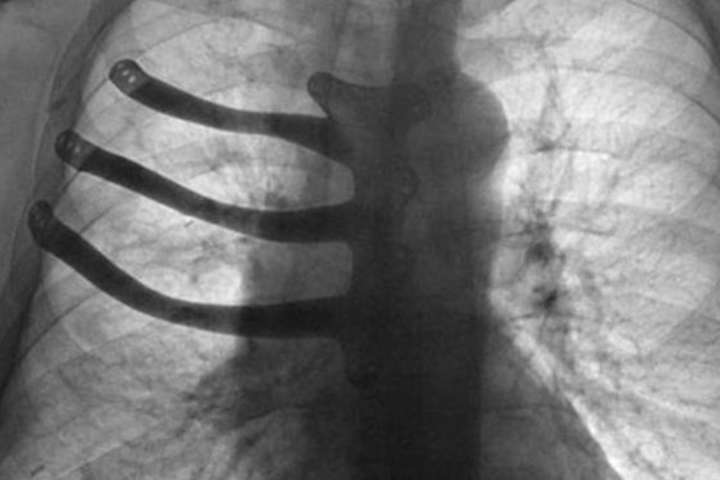

Під час операції з видалення ракової пухлини британські лікарі реконструювали хворому груди за допомогою 3D-принтера.

71-річному Пітеру Меггзу видалили три ребра і половину грудної кістки, помістивши замість них протез.

Ракова пухлина розрослася завбільшки з тенісний м'яч і її видалення спричинило за собою великі ушкодження грудної клітини.

Але завдяки технології 3D-друку лікарі змогли виготовити для хворого індивідуальний імплантат з титанового сплаву.

«Потрібно було вирізати пухлину, а разом з нею видалити частину грудної кістки і три ребра», - розповідає хірург-кардіолог Айра Голдсміт.

«Це загрожувало серйозними ушкодженнями, здатними порушити роботу всієї грудної клітки, реконструювати яку було б дуже складно», - додав лікар.

Титановий імплантат виготовили заздалегідь - за моделлю, яку підготував доктор Голдсміт.